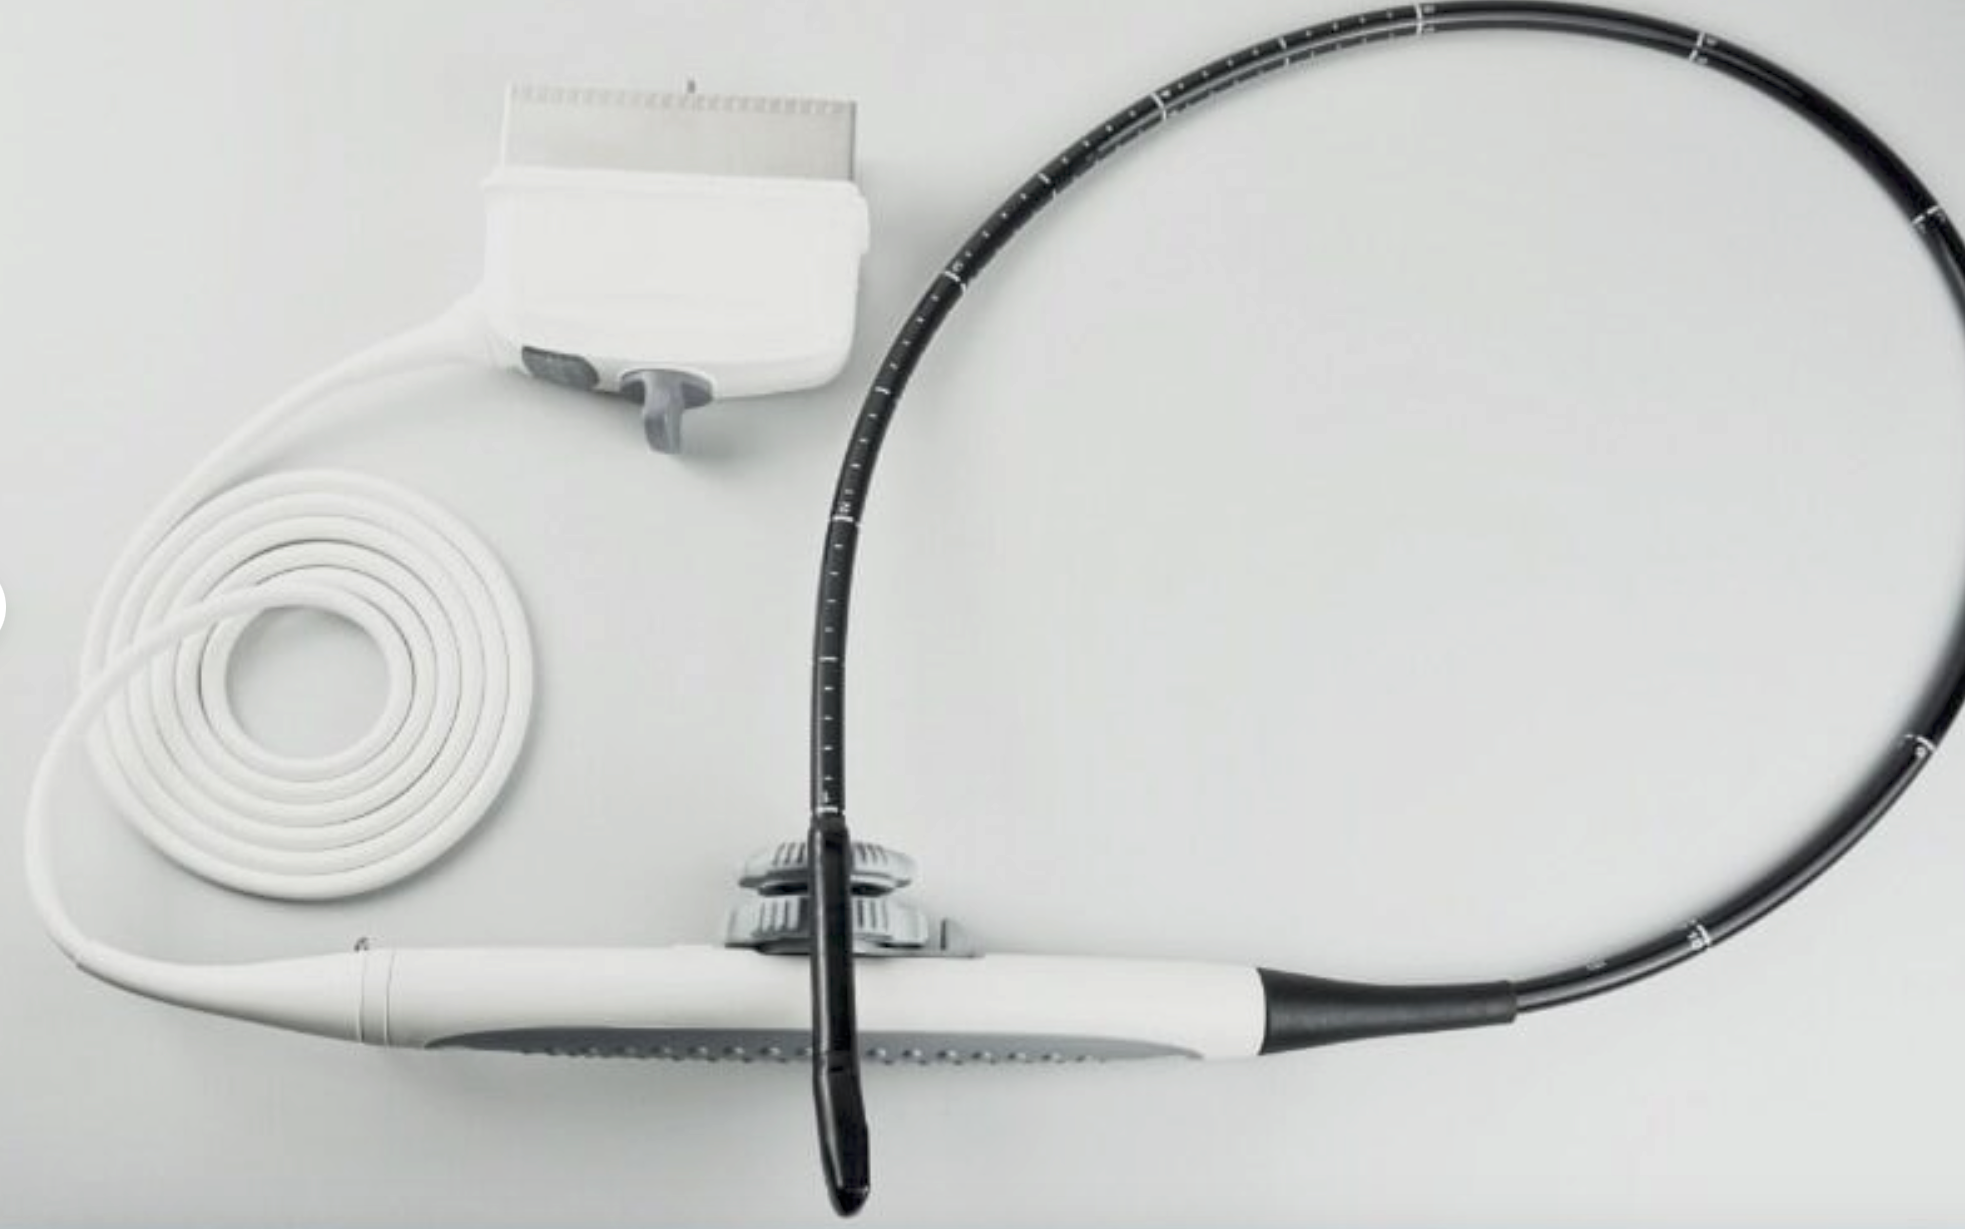

Probe 2: 7.5MHZ Transvaginal probe:gynecologic examination